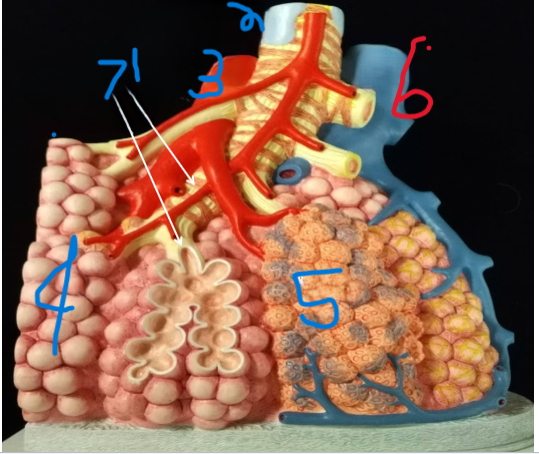

Terminal Bronchiole

What is depicted by #1

Bronchiole with smooth muscle

What is depicted by #2

Pulmonary vein, branch

What is depicted by #3

Alveoli

What is depicted by #4

Pulmonary capillaries

What is depicted by #5

Pulmonary artery, branch

What is depicted by #6

Respiratory Bronchiole

What is depicted by #7